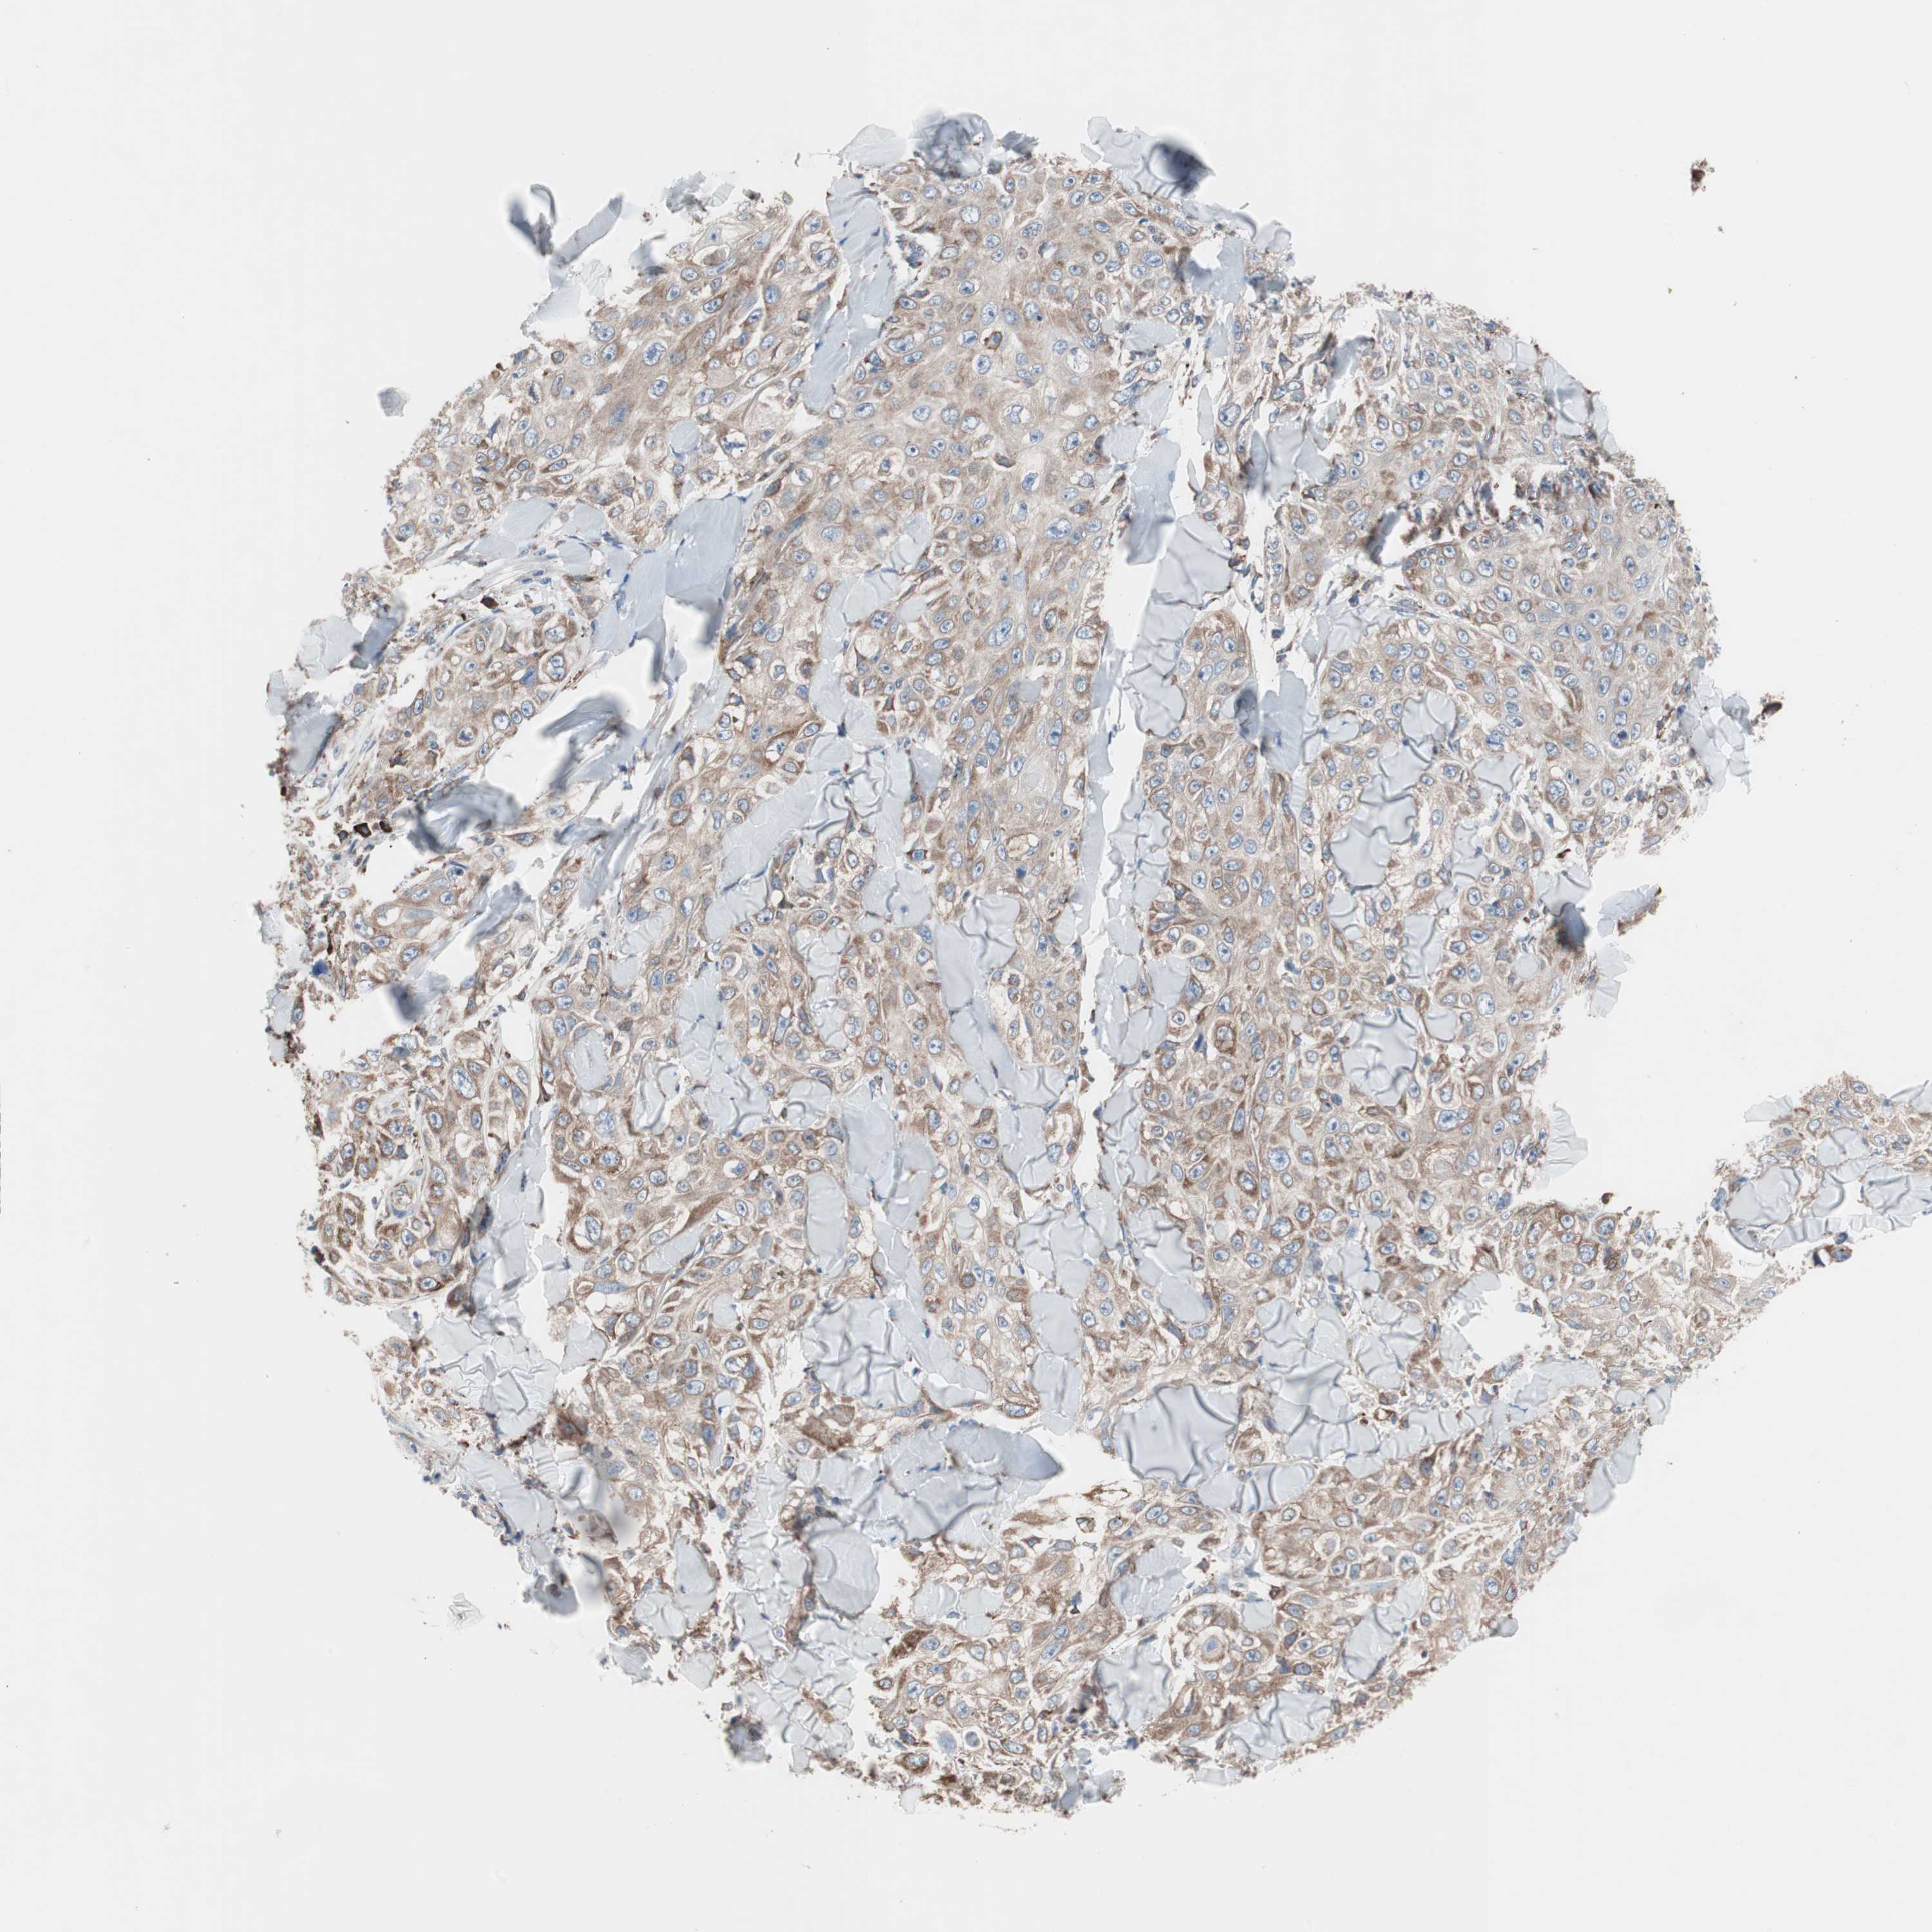

CANCER SKIN CANCER Show tissue menu

Basal cell and squamous cell cancer

SKIN CANCER - Protein expressioni

A mouse-over function shows sample information and annotation data. Click on an image to view it in a full screen mode. Samples can be filtered based on level of antibody staining by selecting one or several of the following categories: high, medium, low and not detected. The assay and annotation is described here.

Each image is clickable and will lead to virtual microscopy that enables deeper exploration of all samples and also displays staining intensity scores, fraction scores and subcellular localization as well as patient and tissue information for each sample.

Antibody CAB009771

Squamous cell carcinoma, NOS

Squamous cell carcinoma, metastatic, NOS

Basal cell carcinoma

Papilloma, NOS

Squamous cell carcinoma in situ, NOS

Adnexal tumor, benign